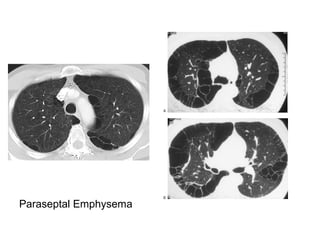

Paraseptal Emphysema

several contiguous layers, this finding can allow

honeycombing to be distinguished from

paraseptal emphysema in which subpleural

cysts usually occur in a single layer